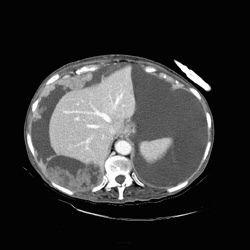

RADIOLOGY: ABDOMEN: Case# 33027: CARCINOMATOSIS. 80 year old female with history of umbilical herniorraphy and abdominal distention. 1) Large amount of ascites with multiple peritoneal based masses as described above. The appearance is consistent with peritoneal carcinomatosis from an as yet undetermined source. The differential diagnosis would include ovarian carcinoma, adenocarcinoma of the gastrointestinal tract, carcinoma of the breast, and renal cell carcinoma. There is apparent metastasis to the umbilical hernia site as well as to a 2 cm right inguinal node. 2) Small bilateral pleural effusions, right greater than left. 3) Simple left renal cyst.